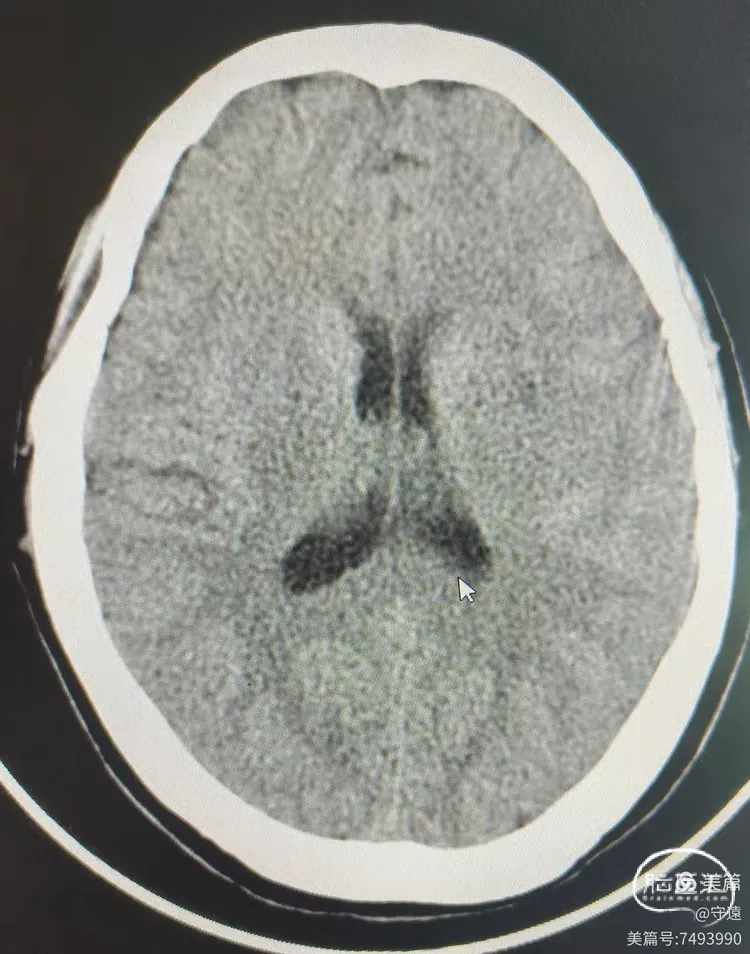

核磁显示:左侧大脑半球多发点状梗塞,MRA显示左侧大脑中动脉M1以这末显影,考虑lCAS病变,给予次替罗非班泵入。

1.核磁显示多发点状梗塞,为低灌注表现,说明患者存在重度狭窄,已有部分代偿。但出现症状性病变,代偿存在不足。